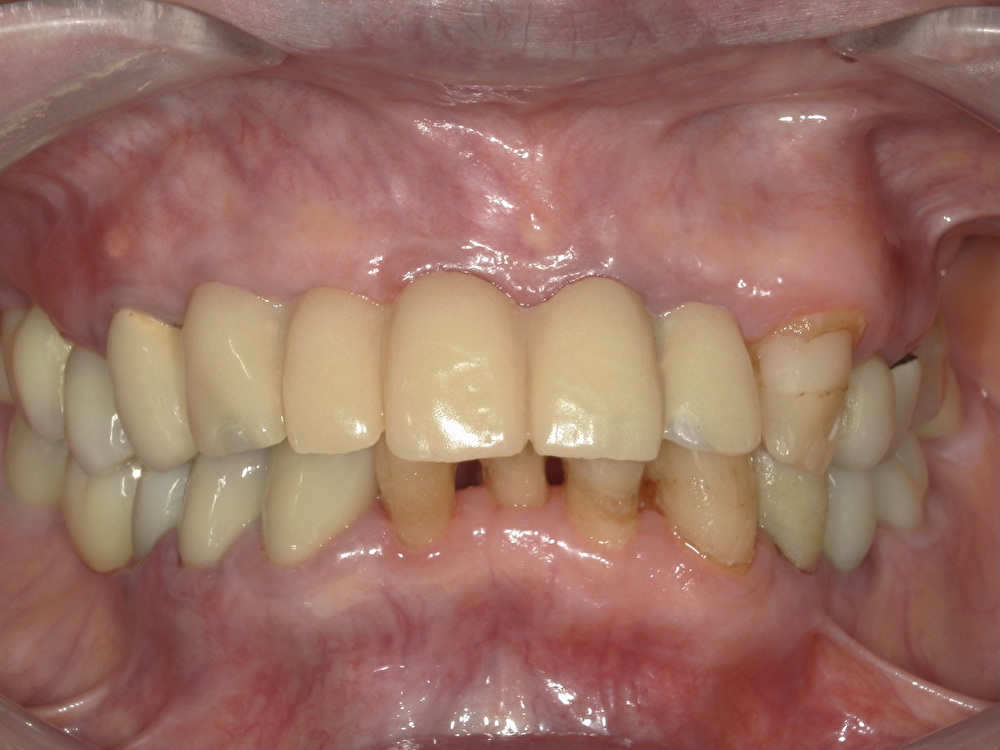

患者様の主訴は『入れ歯の前歯を綺麗に治して、見た目を気にせずに笑いたい。違和感のない前歯になるよう治療したい。』というものでした。術前の状態が以下の写真です。

会話時や笑ったときに入れ歯の金属のバネが見えてしまっており、患者様はとても前歯の見た目を気にしていらっしゃいました。